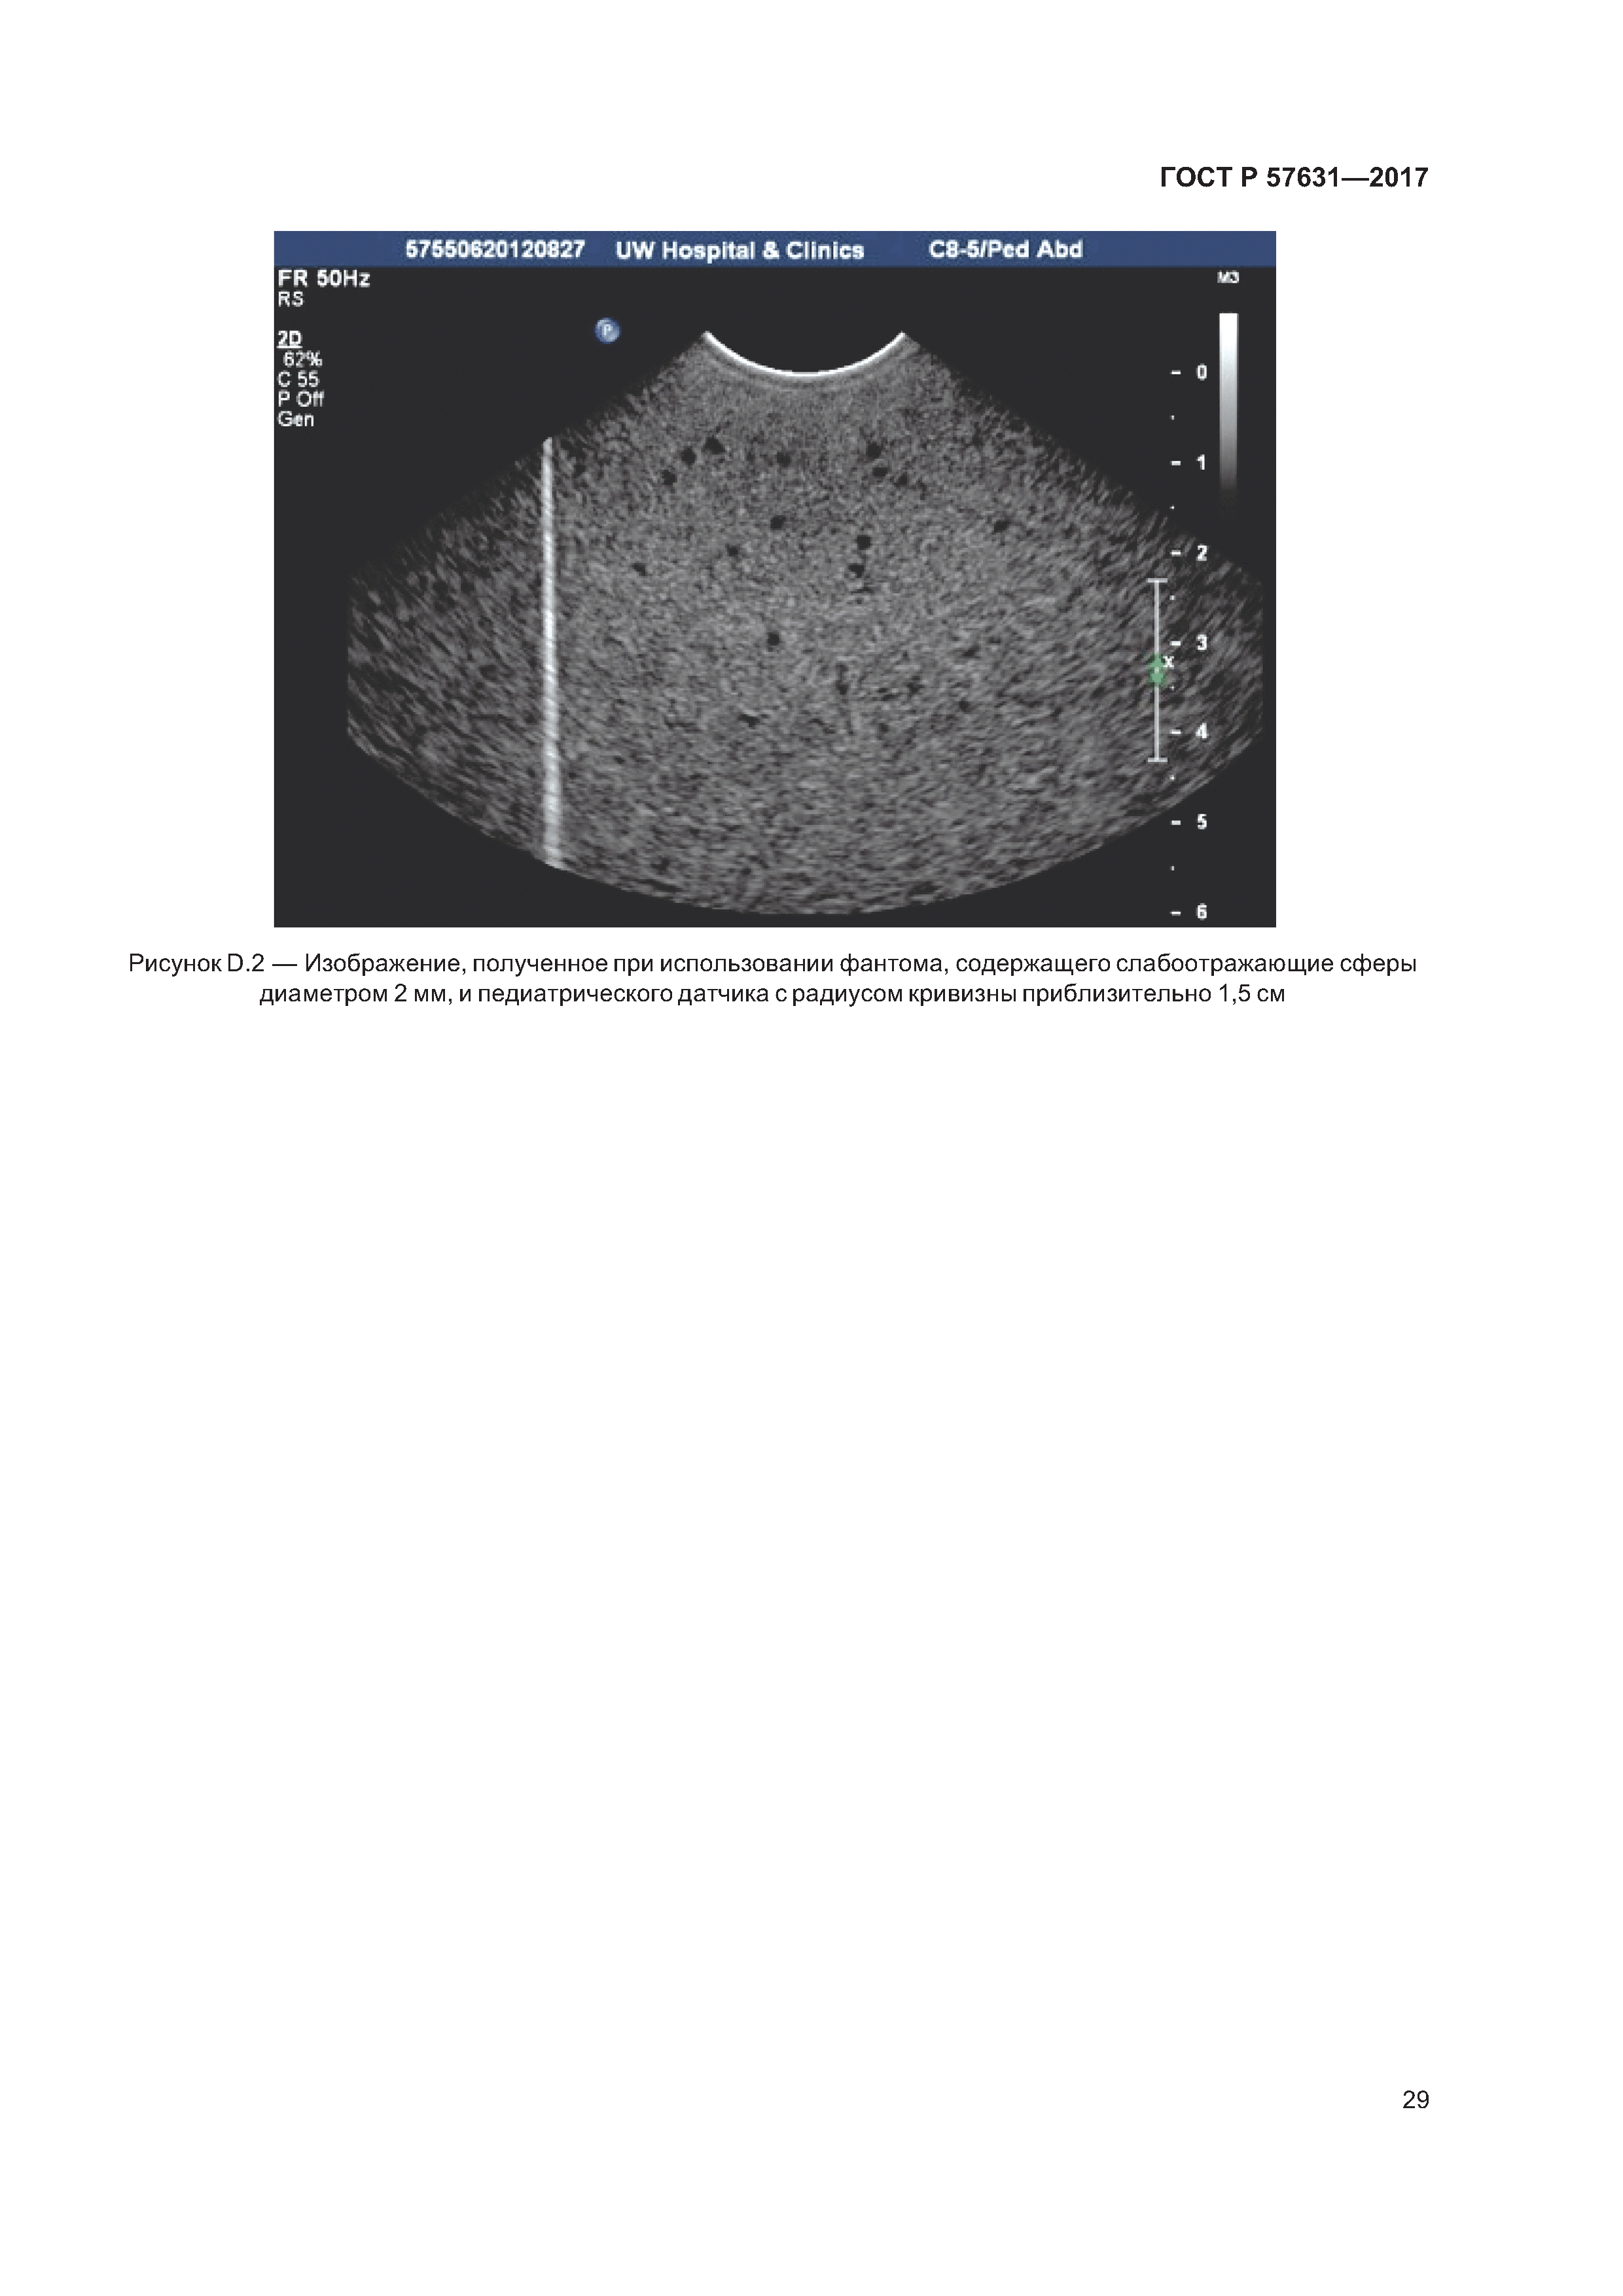

| Оглавление: | 1 Область применения 2 Нормативные ссылки 3 Термины и определения 4 Обозначения 5 Общие условия и условия эксплуатации 6 Необходимое оборудование 6.1 Общие сведения 6.2 Геометрические параметры фантомов 6.3 Ультразвуковые свойства тканеимитирующих (ТИ) фантомов 7 Получение данных, предполагающих случайное пространственное распределение слабоотражающих сфер 7.1 Методика 7.2 Хранение оцифрованных данных изображений 7.3 Файлы оцифровых изображений, получаемые непосредственно со сканера 7.4 Системы архивирования изображений 8 Автоматизированный анализ данных для количественной оценки вероятности обнаружения слабоотражающих сфер 8.1 Общие сведения 8.2 Вычисление средних значений пикселя МРV 8.3 Определение значения ОСШс в заданном интервале глубины Приложение А (справочное) Пример фантома для эксплуатационных испытаний в диапазоне частот от 2 до 7 МГц Приложение В (справочное) Иллюстрации к вычислению значений ОСШс в зависимости от глубины Приложение С (справочное) достаточное число изображений для обеспечения воспроизводимости результатов Приложение D (справочное) Пример фантома для эксплуатационных испытаний в диапазоне частот от 7 до 15 МГц Приложение Е (справочное) Определение положения слабоотражающих сфер в прямоугольной системе координат х, у, z с точностью до D/8 Приложение F (справочное) Испытание на полное внутреннее отражение при использовании плоских отражателей из алюминия и стекла Приложение G (справочное) Результаты испытания на воспроизводимость значений ОСШс в зависимости от глубины для фантома со слабоотражающими сферами диаметром 4 по две сферы на миллилитр Приложение Н (справочное) Результаты оценки зависимости значения ОСШс от концентрации слабоотражающих сфер и глубины для фантомов со сферами диаметром 4 мм Приложение I (справочное) Результаты оценки зависимости значения ОСШс от концентрации слабоотражающих сфер и глубины для фантомов со сферами диаметром 3,2 мм Приложение J (справочное) Сравнение двух разных моделей сканера с аналогичными датчиками и настройками панели управления Приложение К (справочное) Особое рассмотрение 30-датчиков Приложение ДА (справочное) Сведения о соответствии ссылочных международных стандартов национальным стандартам Библиография |